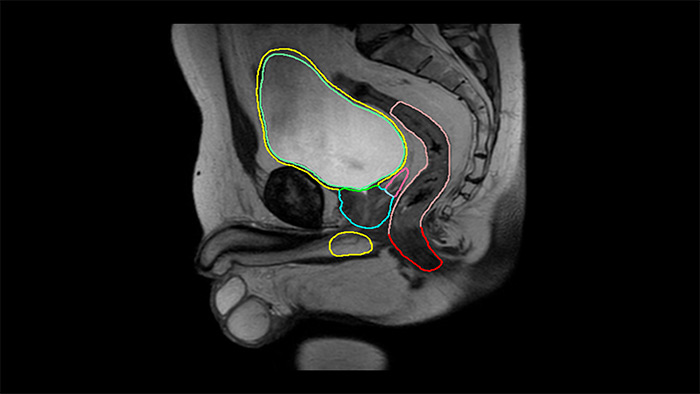

MRCAT Pelvis

MRCAT Prostate + Auto-Contouring